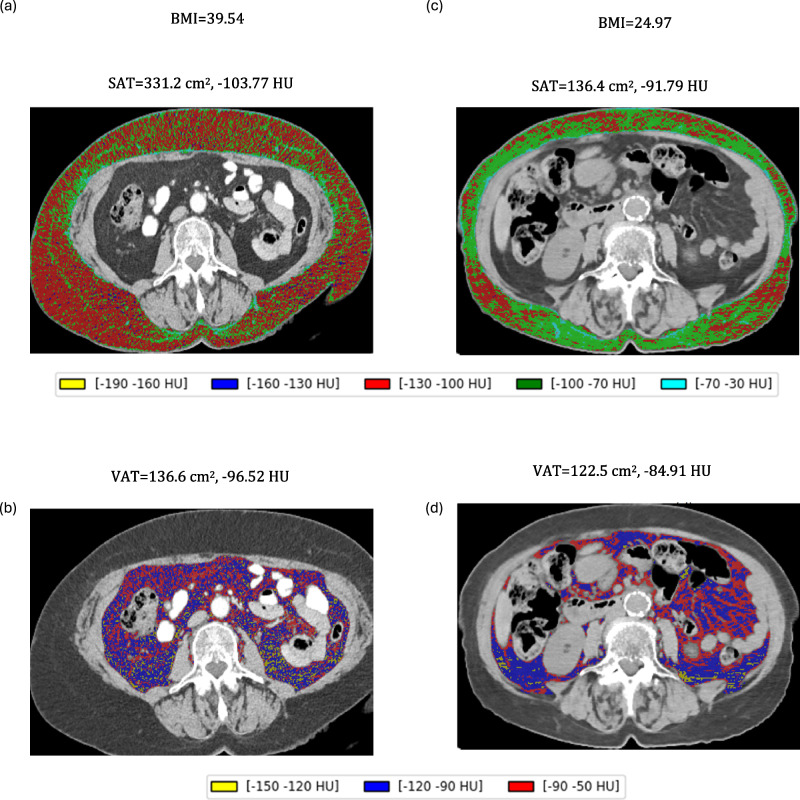

身体成分是癌症患者的重要预测因子,骨骼肌损失和高脂肪与预后不良相关。本研究评估了48例接受曲妥珠单抗德鲁德康治疗的转移性乳腺癌患者的身体成分如何影响治疗效果。在开始治疗前60天内,使用计算机断层扫描,评估骨骼肌、内脏脂肪组织(VAT)和皮下脂肪组织(SAT)。高SAT和VAT区域与剂量减少的可能性显著相关(优势比[OR] = 5.34, p =。OR = 5.52, p = 0.032)。较高的SAT区域与较低的客观反应率相关(OR = 0.22, p = 0.047)。中等SAT和低/中等VAT密度增加了剂量减少的风险。体重指数超过25 kg/m2与较高的剂量减少有关(OR = 4.97, p = 0.016)。这些发现强调了基于身体成分的个性化治疗策略的必要性。

Body composition is an important predictor in cancer patients, with skeletal muscle loss and high adiposity associated with poorer prognosis. This study evaluated how body composition affects treatment efficacy in 48 women with metastatic breast cancer receiving trastuzumab deruxtecan. Using computed tomography, skeletal muscle, visceral adipose tissue (VAT) and subcutaneous adipose tissue (SAT) were assessed within 60 days before initiating treatment. High SAT and VAT areas were significantly associated with a higher likelihood of dose reductions (Odds Ratio [OR] = 5.34, p = .032 and OR = 5.52, p = 0.032, respectively). Higher SAT areas correlated with a lower objective response rate (OR = 0.22, p = 0.047). Medium SAT and low/medium VAT densities increased the risk of dose reductions. A body mass index over 25 kg/m2 was linked to higher dose reductions (OR = 4.97, p = 0.016). These findings emphasize the need for personalized treatment strategies based on body composition.